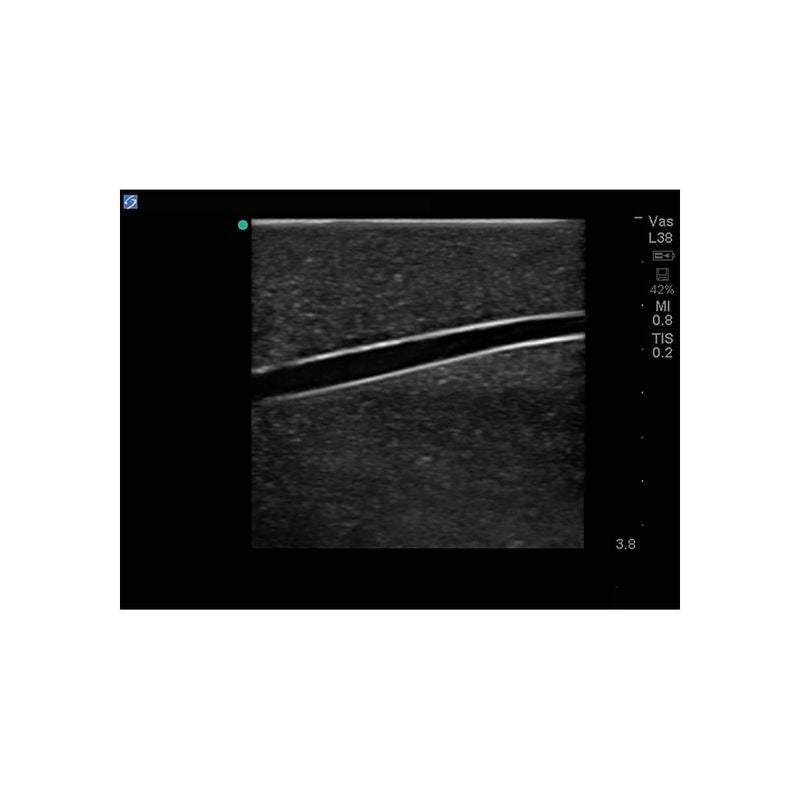

Replacement tissue insert for Central Line and Regional Anesthesia Model (BPHNB670 series).-